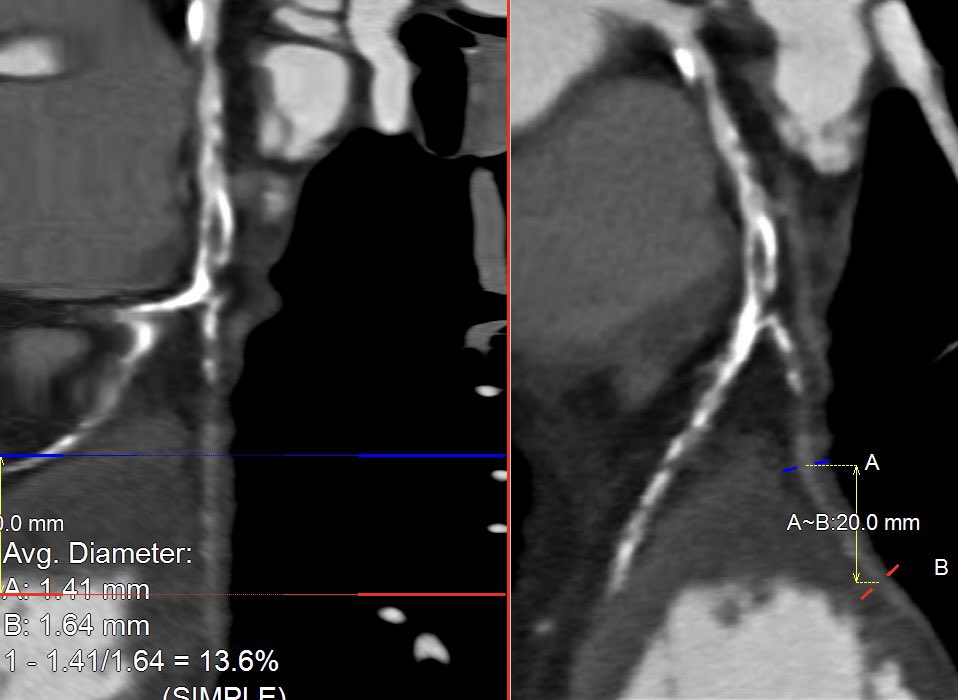

Recent #CTOPCI - surgical turndown, LVEF 20%. CCTA for mapping & plaque evaluation ➡️ CTO ~30mm, heavy Ca+, distal bifurcation. No R->L collaterals. PCI: impella supported, #AWE crossed IP w/ Gaia 3 ➡️ 1.25mm rota to mid segment ➡️ IVUS ➡️NC/CB ➡️ DESx 3 to LAD ostium #CHIP

Recent #CTOPCI - surgical turndown, LVEF 20%.

CCTA for mapping &amp; plaque evaluation ➡️ CTO ~30mm, heavy Ca+, distal bifurcation. No R-&gt;L collaterals.

PCI: impella supported, #AWE crossed IP w/ Gaia 3 ➡️ 1.25mm rota to mid segment ➡️ IVUS ➡️NC/CB ➡️ DESx 3 to LAD ostium

#CHIP